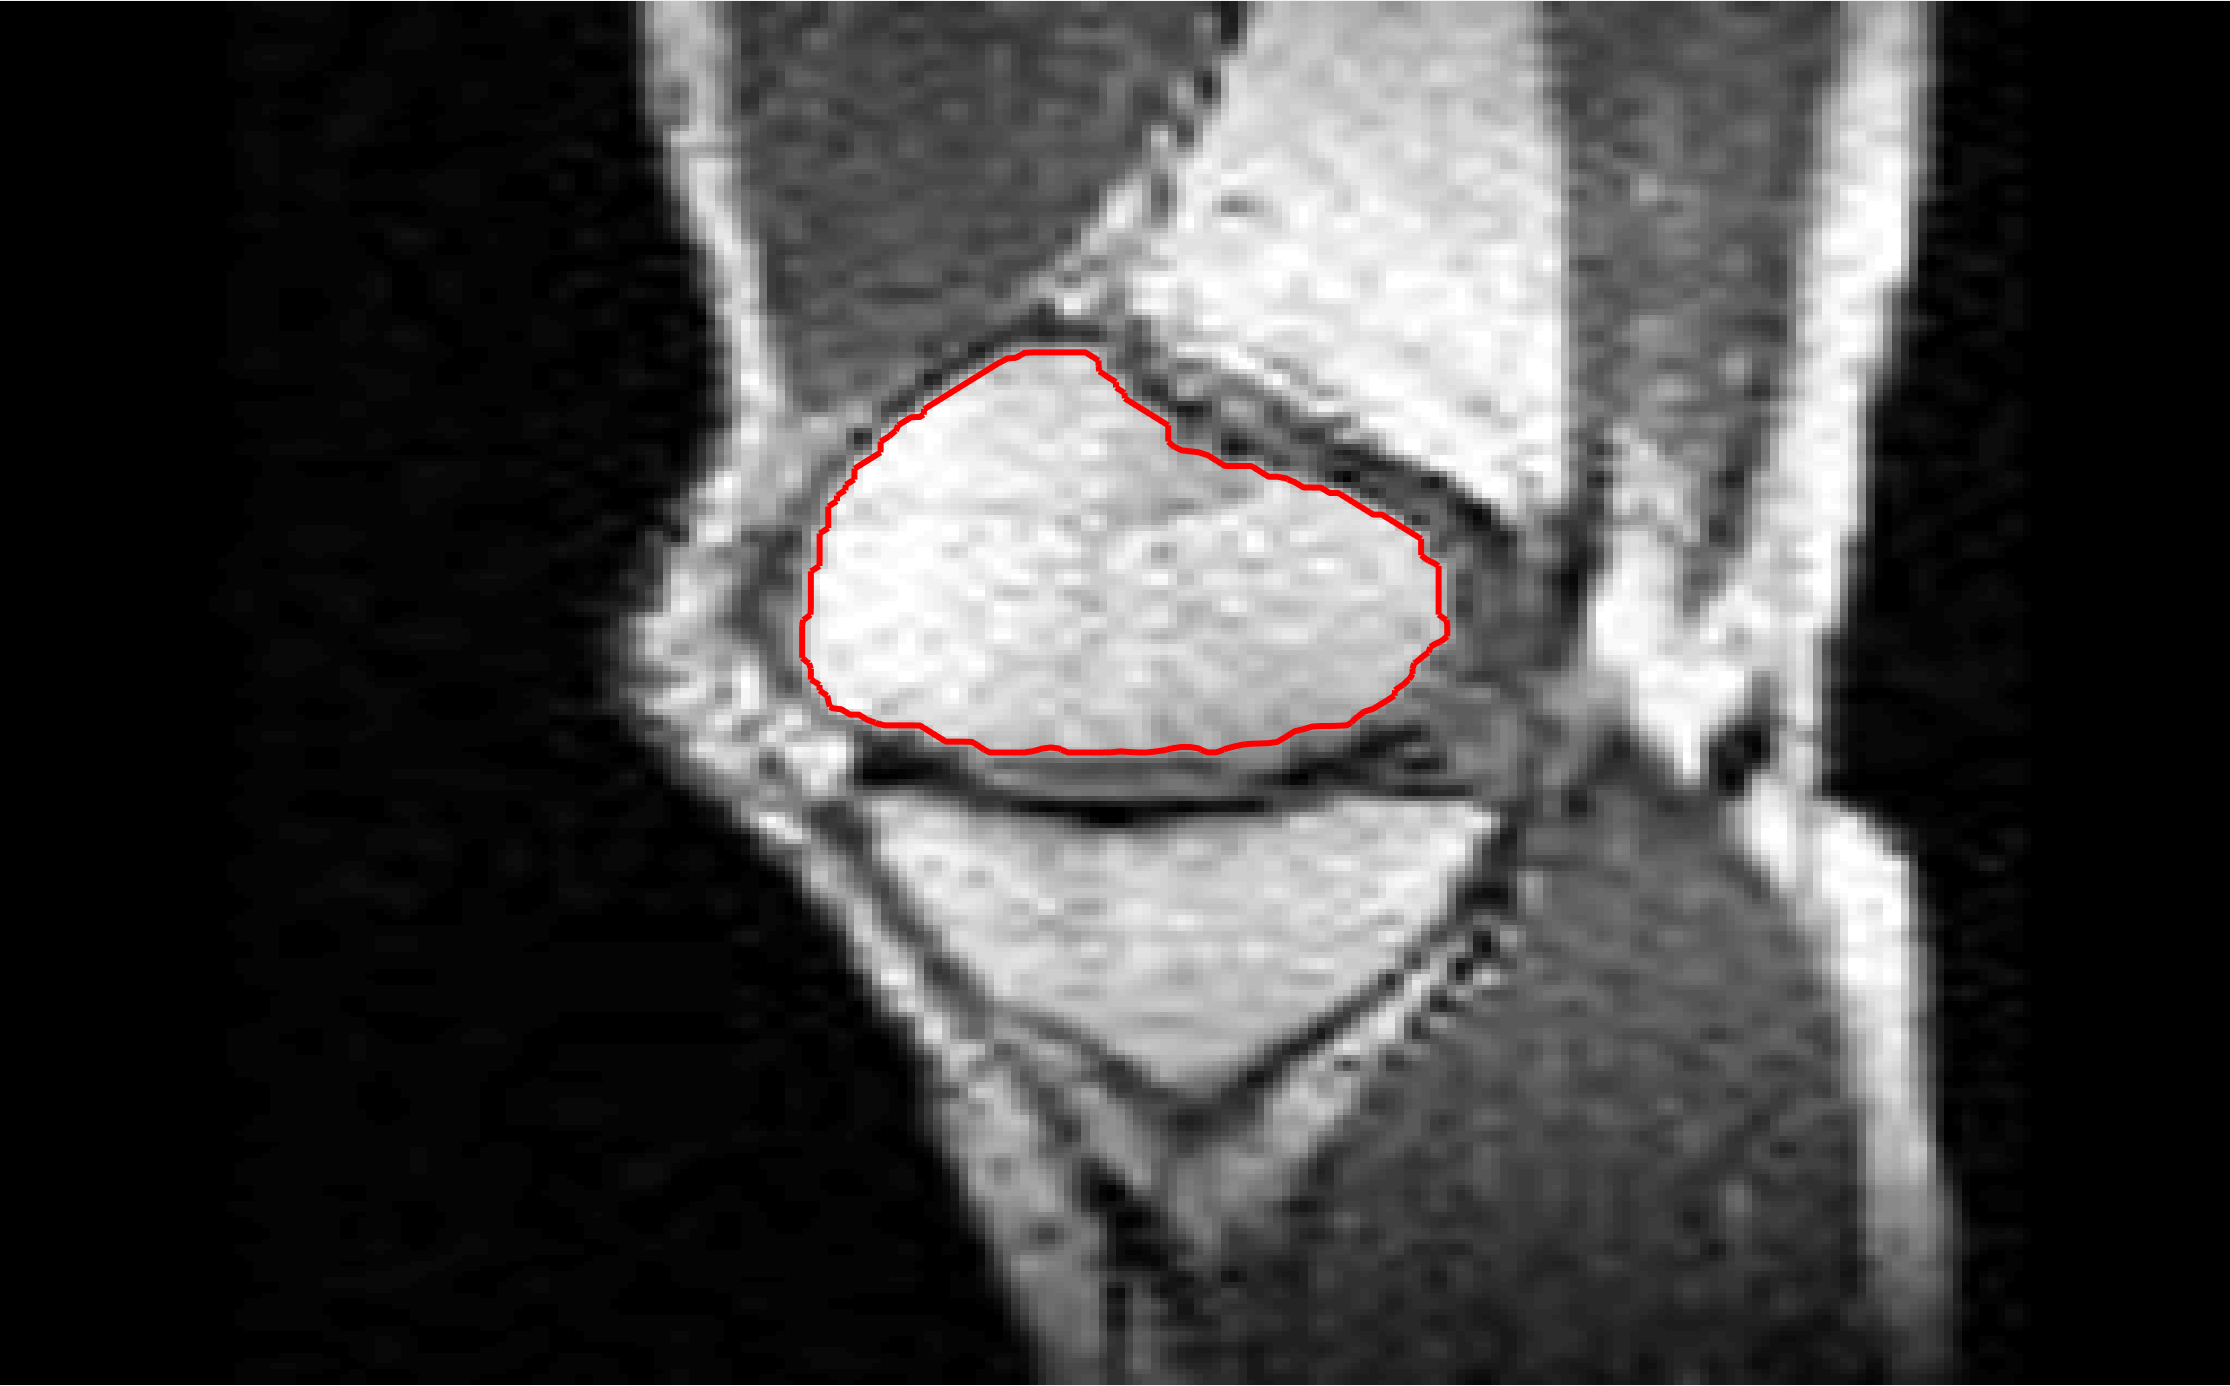

Four sets of test results are shown below. In Test 1 we compare models M1 – M6 to the proposed model M7 for two images which are hard to segment. The first is a CT scan from which we would like to segment the lower portion of the heart, the second is an MRI scan of a knee and we would like to segment the top of the Tibia. See Figure 9 for the test images and the marker sets used in the experiments. In Test 2 we will review the sensitivity of the proposed model to the main parameters. In Test 3 we will give several results achieved by the model using marker and anti-marker sets. In Test 4 we show the initialisation independence and marker independence of the Geodesic Model on real images.

In this test we give the segmentation results for models M1 – M7 for the two challenging test images shown in Figure 9. The marker and anti-marker sets used in the experiments are also shown in this figure. After extensive parameter tuning, the best final segmentation results for each of the models are shown in Figures 10 and 11. For M1 – M4 we obtain incorrect segmentations in both cases. In particular, the results of M2 and M4 are interesting as the former gives poor results for both images, and the latter gives a reasonable result for Test Image 1 and a poor result for Test Image 2. In the case of M2, the regularisation term includes the edge detector and the distance penalty term (see (4)). It is precisely this which permits the poor result in Figures 10(b) and 11(b) as the edge detector is zero along the contour and the fitting terms are satisfied there (both intensity and area constraints) – the distance term is not large enough to counteract the effect of these. In the case of M4, the distance term and edge detector are separated from the regulariser and are used to weight the Chan-Vese fitting terms (see (9)). The poor segmentation in Figure 11(b) is due to the Chan-Vese terms encouraging segmentation of bright objects (in this case), weighting enforces these terms at all edges in the image and near . In experiments, we find that M4 performs well when the object to segment is of approximately the highest or lowest intensity in the image, however when this is not the case, results tend to be poor. We see that, in both cases, models M5 and M6 give much improved results to M2 and M4 (obtained by incorporating the geodesic distance penalty into each). The proposed Geodesic Model M7 gives an accurate segmentation in both cases. It remains to compare M5, M6 and M7. We see that M5 is a non-convex model (and cannot be made convex [39]), therefore results are initialisation dependent. It also requires one more parameter than M6 and M7, and an accurate set to give a reasonable area constraint in (4). These limitations lead us to conclude M6 and M7 are better choices than M5. In the case of M6, it has the same number of parameters as M7 and gives good results. M6 can be viewed as the model M7 with weighted intensity fitting terms (compare (18) and (30)). Experimentally, we find that the same quality of segmentation result can be achieved with both models generally, however M6 is more parameter sensitive than M7. This can be seen in the parameter map in Figure 12 with M7 giving an accurate result for a wider range of parameters than M6. To show the improvement of M7 over previous models, we also give an image in Figure 13 which can be accurately segmented with M7 but the correct result is never achieved with M6 (or M3). Therefore we find that M7 outperforms all other models tested M1 – M6.

Test 2 – Test of M7’s sensitivity to changes in its main parameters. In this test we demonstrate that the proposed Geodesic Model is robust to changes in the main parameters. The main parameters in (20) are and . In all tests we set , which is simply a rescaling of the other parameters, and we set . In the first example, in Figure 12, we compare the TC value for various and values for segmentation of a bone in a knee scan. We see that the segmentation is very good for a larger range of and values. For the second example, in Figure 13, we show an image and marker set for which the Spencer-Chen model (M3) and modified Liu et al. model M6 cannot achieve the desired segmentation for any parameter range, but which can be attained for the Geodesic Model for a vast range of parameters. The final example, in Table 1, compares the TC values for various values with fixed parameters and . We use the images and ground truth as shown in Figures 12 and 13: on the synthetic circles image we obtain a perfect segmentation for all values of tested, and in the case of the knee segmentation the results are almost identical for any , above which the quality slowly deteriorates.